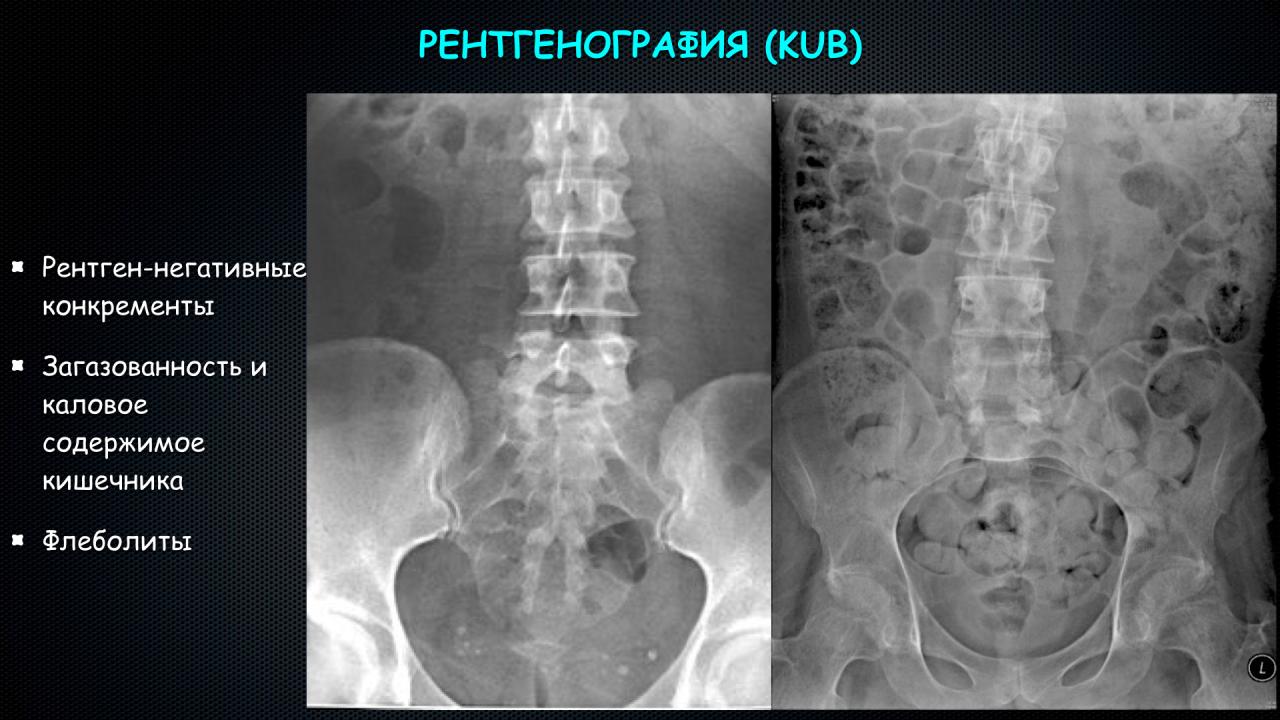

Изображения КТ конкрементов мочевого пузыря